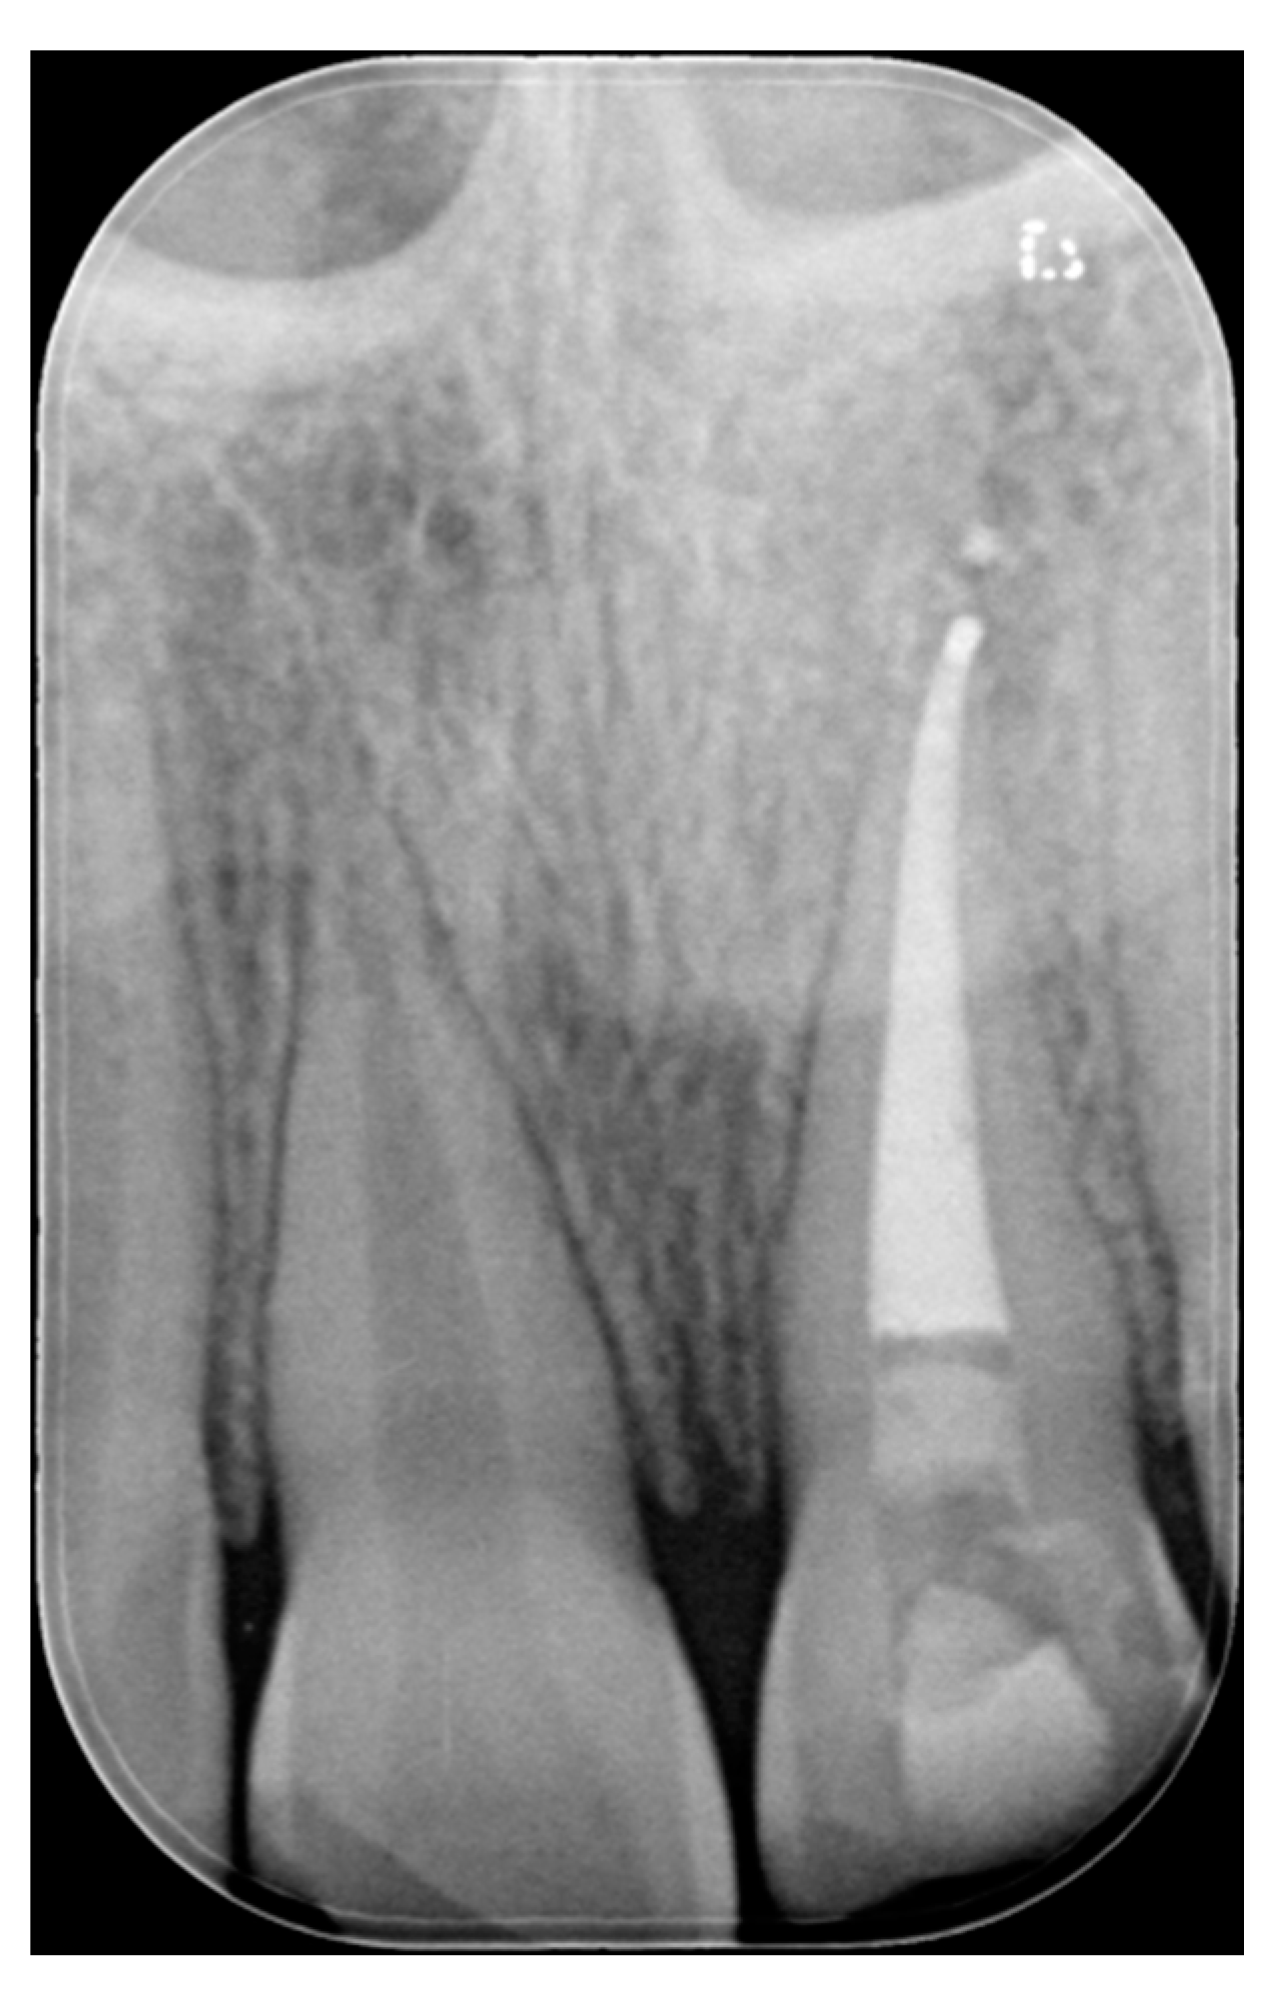

A 27-years lady presented to the dental office after traumatic accident (Figure 30). Tooth #1.1 responded positively to pulp tests (cold and electrical) while Tooth #2.1 showed pulp exposure and continuous bleeding. Endodontic treatment was therefore performed on #2.1 (Figure 31) and direct restoration of both teeth was planned. Shade was selected as described in previous case, using the button-try technique [14]. Even in this clinical case, considered the sufficient ferrule, no post was applied on Tooth #2.1. After isolation and preparation (Figure 32), adhesive procedures were performed using a self-etch two-step adhesive with selective etching procedure (Clearfil SE, Kuraray Noritake Dental, Tokyo, Japan).

Figure 31.

X-ray after endodontic treatment. Reprinted from Restauri diretti nei settori anteriori, G. Paolone, S. Scolavino, © 2021, with permission from Quintessence Publishing Italy.